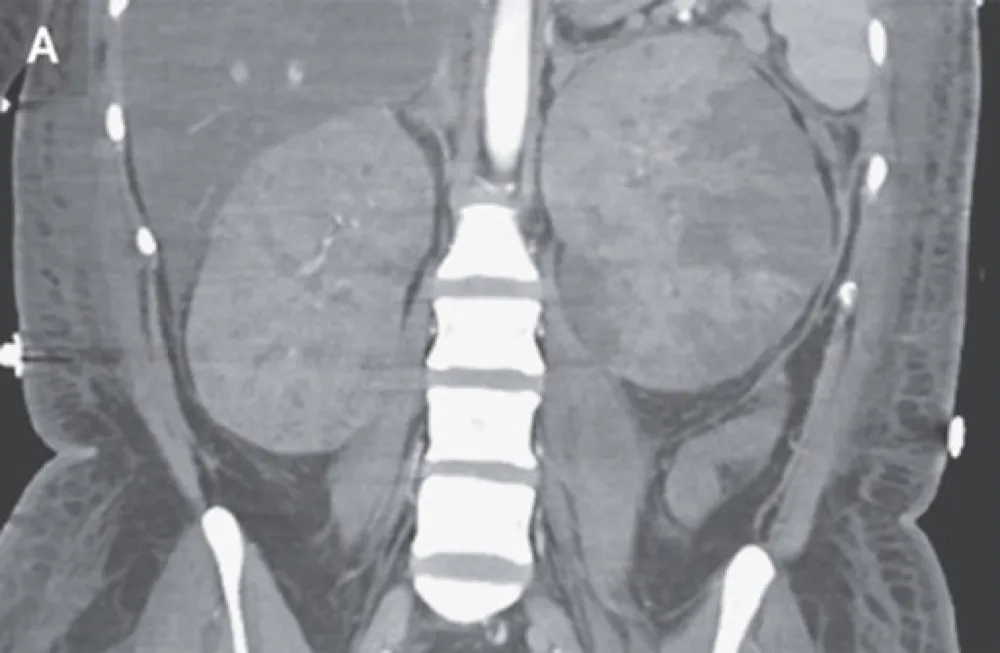

IRA + Icterícia: Um Caso que Exige Investigação Detalhada